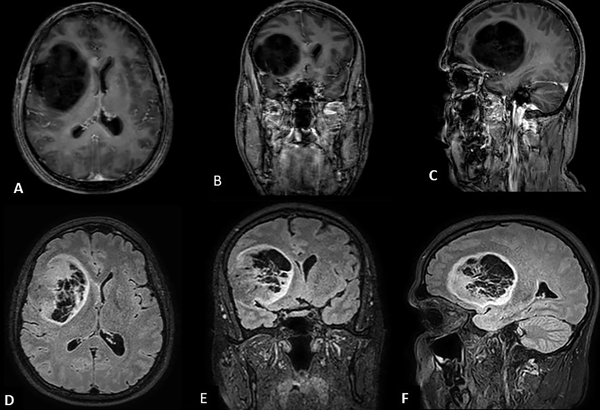

En estudio de resonancia magnética (RM) cerebral con gadolinio (Fig. 1 A, B y C) se define una lesión quística frontal derecha que mide 7.08 cm, x 6.10 cm x 5.28 cm, ocupando un volumen de 114 cm3; presencia de escaso edema perilesional; no se observan realces tras la administración del contraste. En el interior de la lesión se aprecian tabiques intraquísticos que tampoco captan contraste. En secuencia FLAIR (Fig. 1 D, E, F) se puede apreciar aumento en la intensidad de señal en todo el borde de la lesión (“signo del anillo”) y a nivel del entramado trabecular.

Fig.1. Resonancia magnética prequirúrgica, secuencia T1 gadolinio, vista axial (A), coronal (B) y sagital (C). Secuencia FLAIR, vista axial (D), coronal (E) y sagital (F), con el signo del anillo.

Los TND aparecen en la resonancia como quistes lobulados, bien delimitados, localizados en la corteza cerebral. La extensión a la sustancia blanca subcortical en casos como éste se considera rara.5 Son hipointensos en ponderación T1 e hiperintensos en T2. Es frecuente la ausencia de edema perilesional, efecto de masa sobre las estructuras de la línea media y el realce de contraste es poco apreciables. Los tabiques intraquísticos son un hallazgo común y el “signo del anillo” (borde hiperintenso en la periferia de la lesión) son observados en la secuencia FLAIR.5 La espectroscopia suele mostrar una disminución del pico de N-acetil-aspartato (NAA) y la relación NAA/ Cho (colina) normal, alto índice de mioinositol/ creatina. Estas características ayudan a identificar la lesión de TND y a distinguirla de otros gliomas de bajo grado.3,4,5